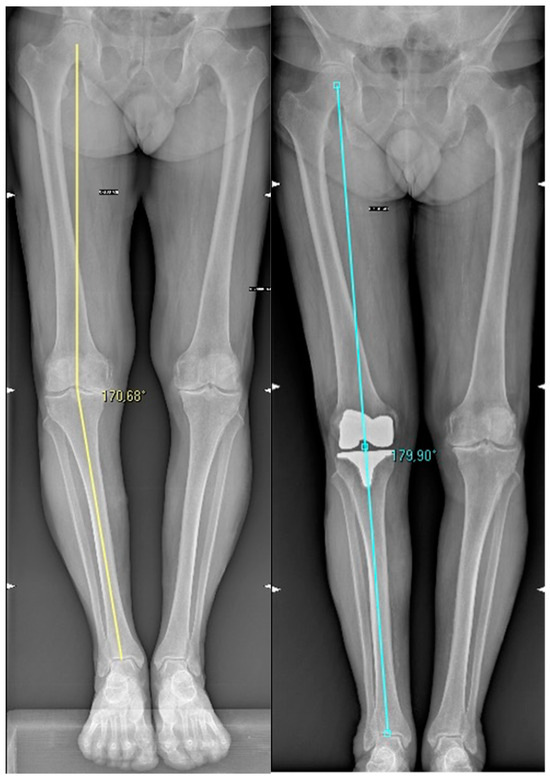

| Hip-Knee Angle (HKA) | 5.3 ± 8° varus | 0.4 ± 3.4° valgus | <0.0001 |